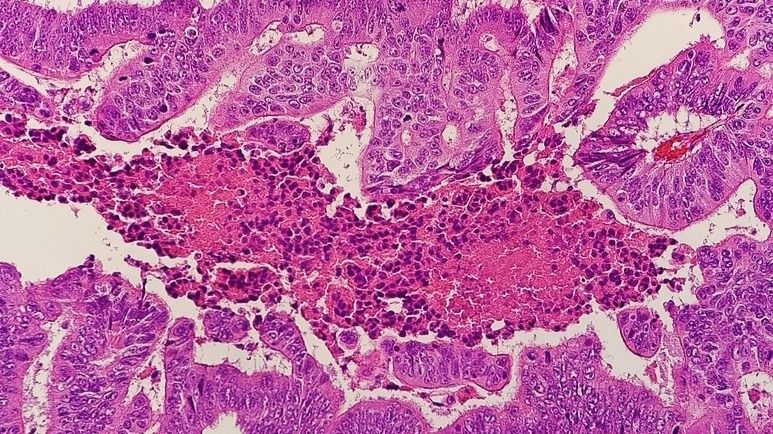

Identificado un nuevo gen que influye en el crecimiento del cáncer de colon

La identificación de un nuevo gen, que definen como esencial para el crecimiento del cáncer de colon, es el nuevo hallazgo de un equipo interdisciplinar de científicos y clínicos de Estados Unidos. Como en otros tumores malignos, la inflamación juega un papel clave.

Células vivas de cáncer de colon

Para llevar a cabo este estudio, los investigadores analizaron tejido tumoral vivo y tejido sano circundante inmediatamente después de las cirugías de 15 pacientes con cáncer de colon. Al preparar y analizar células vivas permitió a este equipo ver el microambiente y los impulsores génicos y biológicos del cáncer de colon.